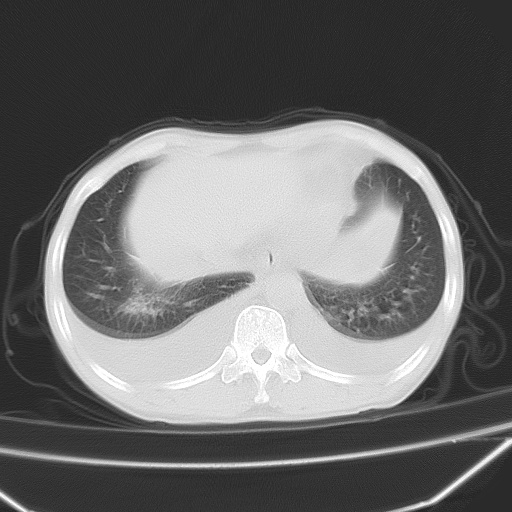

男、42岁、咯血3天。既往有甲亢、贫血、血尿蛋白尿史多年。血象:wbc:6.   中性粒:70.6%。

双肺野对称性磨玻璃影,分布于内中带,双侧胸水,患者有咯血。

双肺野广泛对称性磨玻璃影、实变影,以肺门为中心,主要分布于内中带,符合典型肺泡性肺水肿;伴双侧胸腔少量游离积液。结合患者既往病史且咯血就诊,支持多因素(尿毒症等)所致之肺水肿、肺出血、胸水;影像表现暂不考虑心源性水肿,且症状也不太符。需密切随诊结合临床治疗等进一步明确。